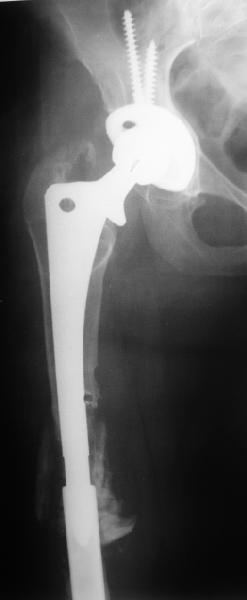

Female, rheumatoid, THA in 2003, car accident in 2006, failed plating. Nailing in Oct 2007. The nail is solid with hollow proximal part where the stem is docked. Last images are in 1 year after

nailing.

The femur responded by failure to Mennen plating (DePuy Bridge plate). So i would add that the ability to unite is realized in mechanically and biologically sound conditions.